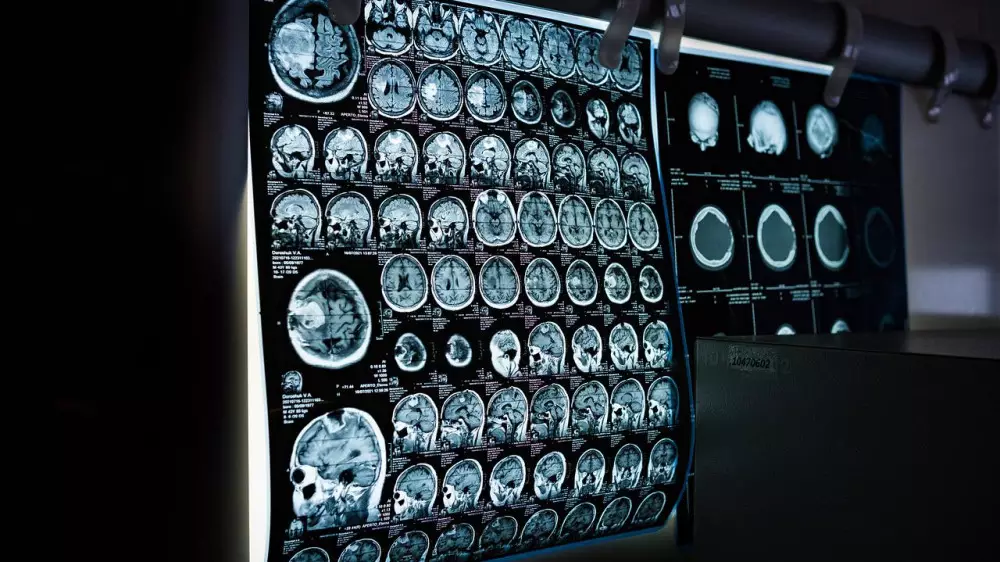

Специалисты набрали 40 добровольцев в возрасте 20-40 лет. Их мозг просканировали утром, днем и поздним вечером методом магнитно-резонансной спектроскопии (МРС).

Средняя температура мозга составила 38,5 градуса, что более чем на два градуса выше температуры, измеренной под языком. Поверхность мозга обычно была холоднее, тогда как более глубокие структуры мозга часто нагревались выше 40 градусов (рекорд за время исследования - 40,9 градуса). У всех людей температура мозга постоянно менялась в зависимости от времени суток почти на 1 градус, при этом самая высокая наблюдалась днем, а самая низкая - ночью.